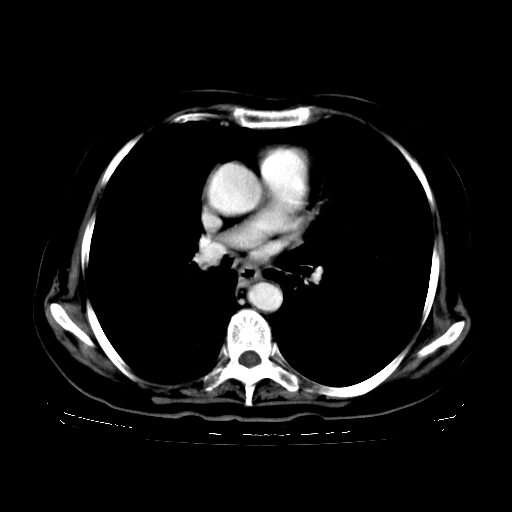

女,70岁,咳嗽、咳痰一个月,低热一周。

1.左上肺结核,部分纤维化。右肺中下叶部分肺不张,内见液化、坏死及点状钙化,右中下叶支气管壁增厚、管腔狭窄,见多个点状钙化,结合临床考虑支气管内膜结核,建议痰检查抗酸杆菌并参考血沉。两肺多个小圆点状高密度灶,境界模糊,多考虑结核肺内播散。但本人年龄较大首先应支气管镜检以除外右肺癌。

2.胸主动脉夹层。